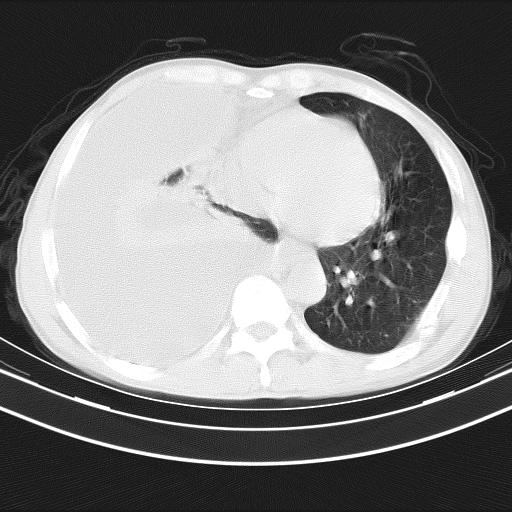

男性,44岁,结核病史多年。现胸闷气短,咳嗽,偶咳血。

右侧胸腔积液

右肺下叶不张

双肺多发结节影最分空洞形成考虑占位不除外结核

双肺陈旧性病变

1、右侧大量胸腔积液伴右肺压缩性膨胀不全,建议抽液治疗后复查 2、两肺继发性tb伴空洞形成。

1)两肺继发性肺结核伴空洞形成,左肺多发性结核球。2)右侧大量胸腔积液伴右肺部分膨胀不全。3)纵隔淋巴结肿大。